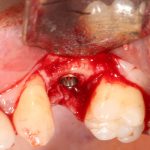

Забор костного фрагмента проводится с наружной косой линии с помощью ультразвукового пьезохирургического инструмента. Ничего сверхнового и супернеобычного тут нет, совершенно стандартная методика. С той лишь разницей, что молоток для этого используют только фашисты и только в гестапо использовать не нужно, всё делается усилием и ловкостью рук.

Нюансы начинаются с обработки принимающего ложа. Да-да, уважаемые друзья, одна из причин некроза блоков, их чрезмерной атрофии и прочих проблем — в отсутствии обработки принимающего ложа. Некоторые делают дырки, но правильнее и эффективнее поступить так:

то есть, просто снять слой кортикальной пластинки с участка, к которому будет фиксироваться костный блок. Почему? Читайте здесь>>.